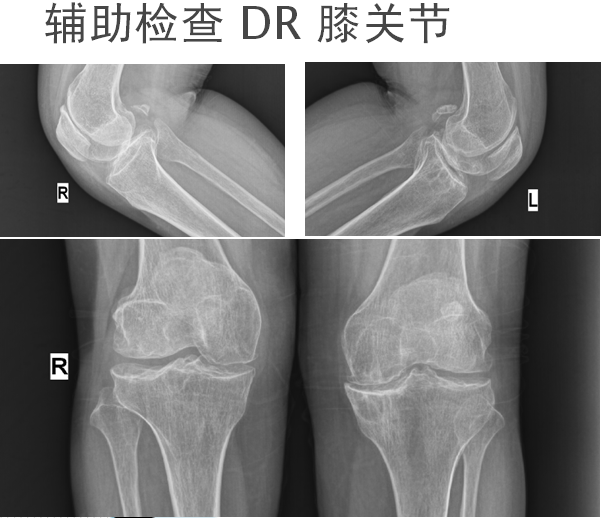

患者:何某某,女,52岁。出生成长于大骨节病流行病区

主诉:反复四肢多关节疼痛伴活内受限30﹢年

现病史:自述30﹢年前无诱因出现双踝、双膝、双髋、双腕关节隐痛,受凉、晨起疼痛明显。并感四肢僵硬感,保暖、适当活动可减轻。于当地医院就诊,诊断为“骨性关节炎”,予药物(具体不详)治疗,疼痛可暂时减轻,但停药后疼痛反复,并逐渐伴上述关节活动受限。患者间断于外行理疗对症,症无完全缓解。不伴游走性关节红肿热,不伴低热、盗汗、进行性消瘦、夜间痛甚等。为进一步治疗,遂于今日入我院。

1.大骨节病

2.双踝、双膝、双髋骨性关节炎